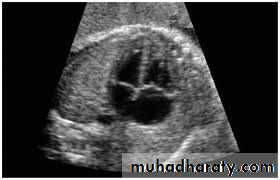

Antenatal diagnosis

Fetal anomaly scan is performed between 18 and 20 weeks' gestation. If an abnormality is detected, detailed fetal echocardiography is performed by a paediatric cardiologist, who also checks any fetus at increased risk, e.g. where Down's syndrome is suspected, where the parents have had a previous child with heart disease or where the mother has C.H.D. The continuation of pregnancy and delivery then planned.

3-Echocardiography

The location and size of the atrial defect are readily appreciated by two-dimensional scanning . The shunt is confirmed by pulsed and color flow Doppler .